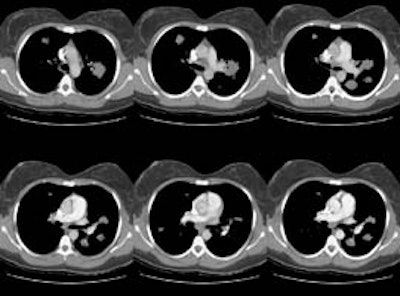

HRCT images:

(Click small pictures to view larger radiographs)